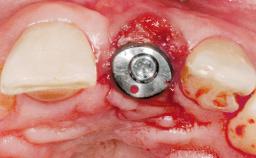

Immediate Placement of an Implant in a Maxillary Left Central Incisor Site

A 33-year-old female patient presented with an upper left central incisor that required extraction after a failed endodontic therapy. The tooth had been traumatized when the patient was a teenager and had undergone several endodontic treatments, including two apicectomy procedures. The patient was in good health and did not smoke. Clinical examination showed that the patient had a high lip line. In full smile, the gingival margins of the upper teeth were visible to the first molars. The gingival margins of central incisors 11 and 21 were only just showing. Examination of tooth 21 confirmed that the tooth was mobile and had hypererupted by 1 mm.

Placement Protocol Immediate implant placement

Tooth Site Maxillary incisor or canine

Socket Morphology Single-root socket

Socket Integrity Damage to one or more bone walls